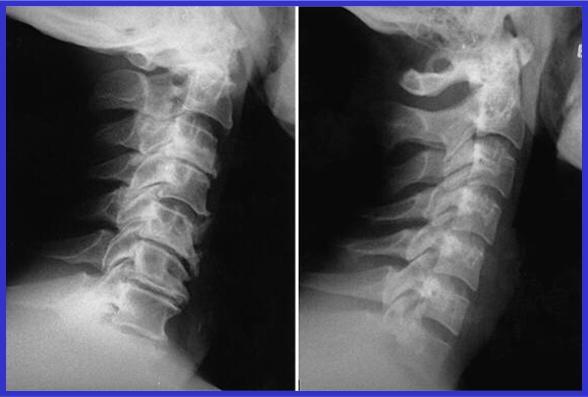

颈椎病X线片特征

CT扫描从颈椎横断切层显示椎管、脊髓及其相互关系